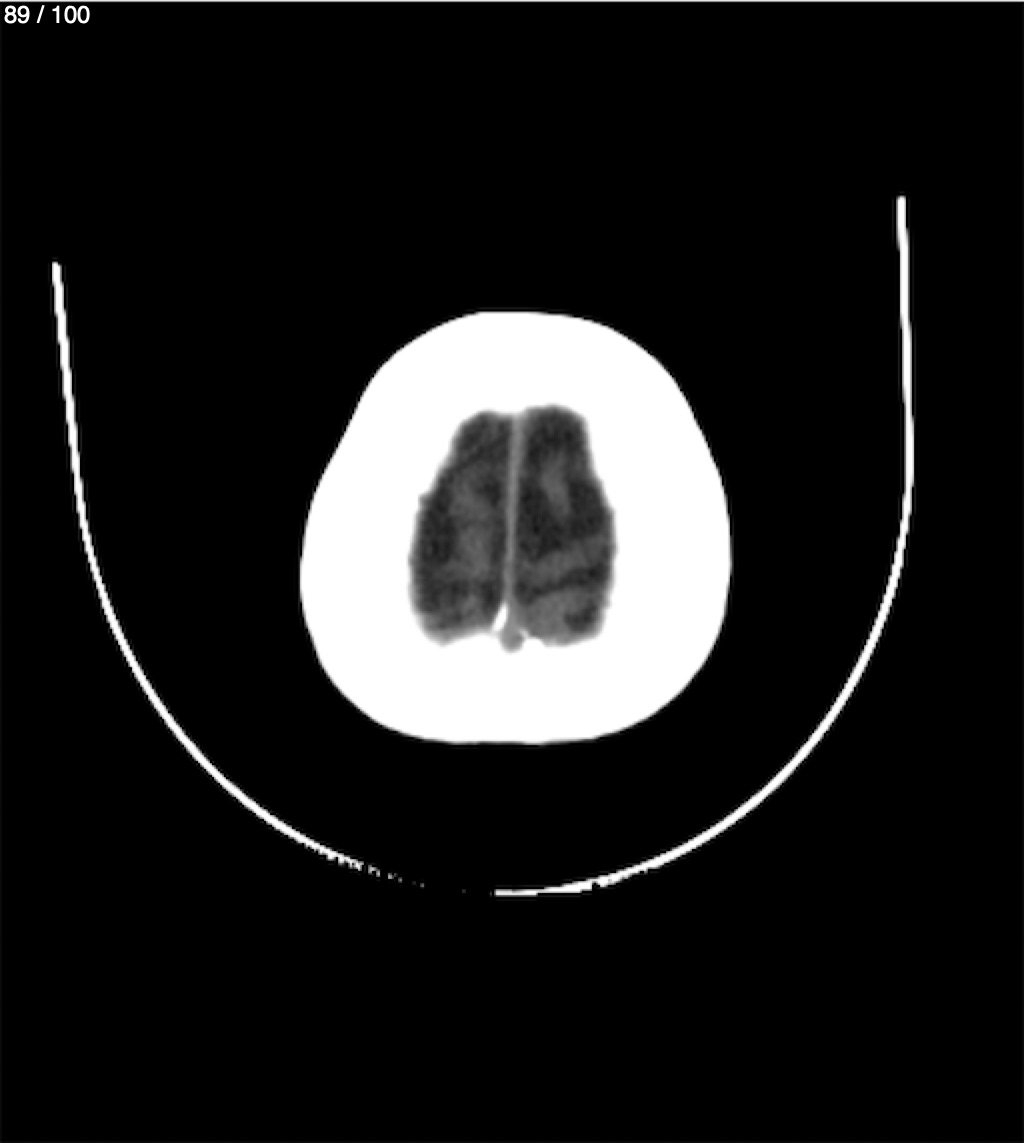

Catarino Perez Escobar 85A - T.C Craneo